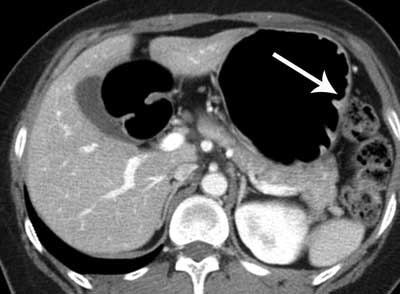

The researchers undertook a retrospective study to evaluate the accuracy of CT gastrography for determining the depth of mural invasion in patients with gastric cancer. CT scans were performed using a 64-slice system (LightSpeed, GE Healthcare). Before the scan, 10 mg of butylscopolamine bromide (Buscopan, Boehringer Ingelheim) was injected intramuscularly to minimize the peristaltic bowel movement and relax the bowel wall. Two packs of effervescent granules (Taejoon Pharmaceuticals) with a small amount of water were administered orally to distend the gastric lumen.

The degree of gastric distension was considered to be adequate when the gastric lumen was distended greater than 50% of the expected maximal luminal distension. Single-phase (portal venous phase) contrast-enhanced CT was performed after intravenous injection of 100 to 150 mL of iodinated contrast material with a power injector (Empowered CTA, E-Z-EM) at a rate of 3 mL/sec through an antecubital vein. The total amount of injected contrast material was adjusted according to the body weight of the patients (2 mL/kg).

Overall, gastric cancer was identified in 123 (96.9%) of the 127 cancers on the CT images. Four undetectable cancers on CT were pathologically staged as T1a (n = 3) and T1b (n = 1), respectively. In cases of early gastric cancer (EGC), 56 (73.7%) of the 76 cancers were visible on both the 2D and the 3D images, whereas EGC was identified only on the 2D and the 3D images in two (2.6%) and 14 (18.4%) cancers, respectively.

"All the AGCs [advanced gastric cancers] were visualized on both the 2D and the 3D images. With respect to the pattern of the gastric mural layering at the site of the gastric cancer and the adjacent normal gastric wall, among 109 gastric cancers that were detected on the 2D images, five (4.6%) and 104 (95.4%) cases were classified as single-layered and multilayered, respectively," the authors wrote.

Most patients (95.4%) showed a multilayered structure of the gastric wall around the lesion site. This observation may be because the gastric wall infiltrated by the tumor becomes thickened and/or stiff, which may negatively affect the distensibility at the site of the gastric cancer and the adjacent normal gastric wall. Alternatively, tumoral infiltration into the gastric wall may be accompanied by inflammatory or edematous change beneath the cancer, which may result in the exaggeration of the multilayered structure of the gastric wall.